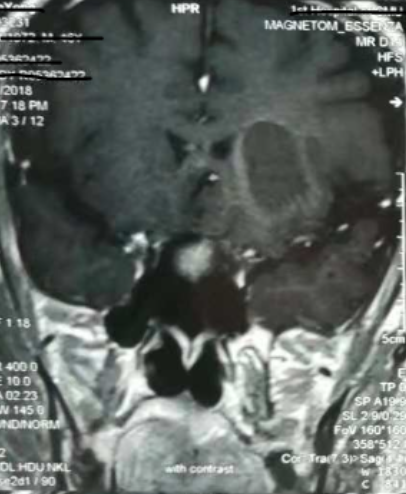

增強核磁提示:血腫液化周邊增強